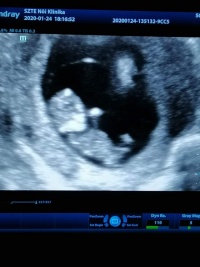

Ki mikor megy legközelebb dokihoz? Ti akkor mostanság mentek/vagytok túl a 12. heti uh-kon, ugye?